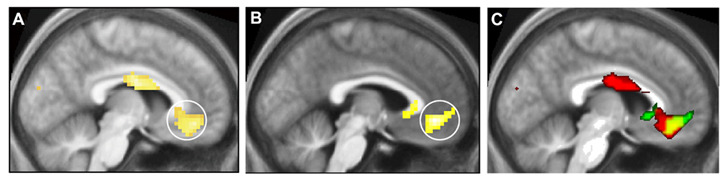

It has recently been discovered that there may be a neurological basis to beauty. This was found when brain images of people familiar with mathematics were compared with people who were shown beautiful art or music.

In the study, published earlier this year, researchers at the University College of London analyzed the brains of 15 mathematicians as they viewed 60 mathematical formulae, using magnetic resonance imaging (MRIs). The subjects were tasked with rating each formula on how beautiful they perceived it to be.

Then, the researchers observed that different areas of the brain were activated, depending on whether a formula was considered to be beautiful, ugly or neutral.

They found that the experience of mathematical beauty activated the same part of the emotional brain, mainly the medial orbitofrontal cortex -- the same areas triggered by music and art!

This study highlights the fact that math is a very beautiful thing! The most beautiful formulae were found to be Euler’s identity and the Pythagorean identity. Can aesthetic experiences be quantified? The answer appears to be: Yes!

- Image: by Tomohiro Ishizu and Semir Zeki. Cortical Activation responding to beauty of math.

- Image: by Semir Zeki and Hideaki Kawabata. Medial Orbito-frontal Cortex Activation in Response to Beauty.